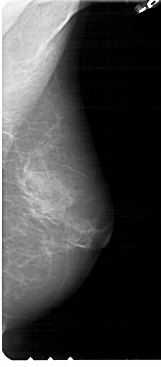

A_1946_1.RIGHT_MLO

RIGHT_CC LINES 3901 PIXELS_PER_LINE 1786 BITS_PER_PIXEL 12 RESOLUTION 43.5 NON_OVERLAY